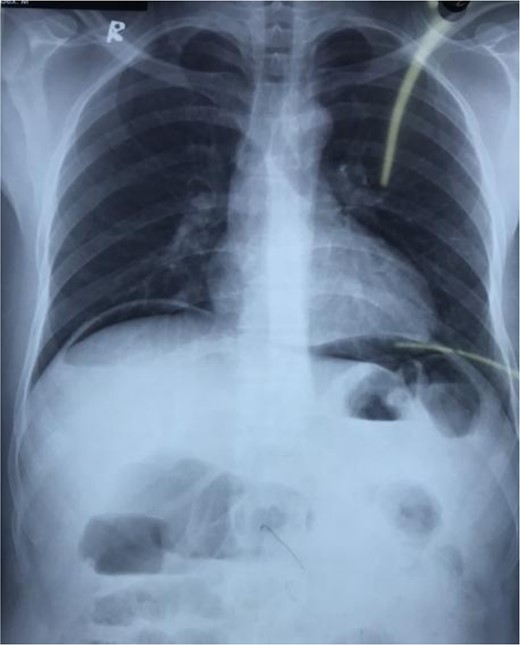

Due to inadequate healthy omentum for graft purposes, the falciform ligament was freed from the anterior abdominal wall and its free end was utilized as a graft to repair the perforation site with polyglactin 3–0 sutures (Fig. 2). Confirmation of no leakage was done by pushing air from nasogastric (NG) tube. The wound was closed after thorough peritoneal lavage with a drain placed in Morrison’s pouch. His postoperative course was uneventful. NG tube and abdominal drain were removed on the third and seventh postoperative day, respectively. He was discharged with triple therapy and 1 month of proton pump inhibitor. At a follow-up in the Outpatient department after a month, he was doing well with no complications.

Falciform ligament used as a graft to repair the perforation site using polyglactin 3-0 sutures.